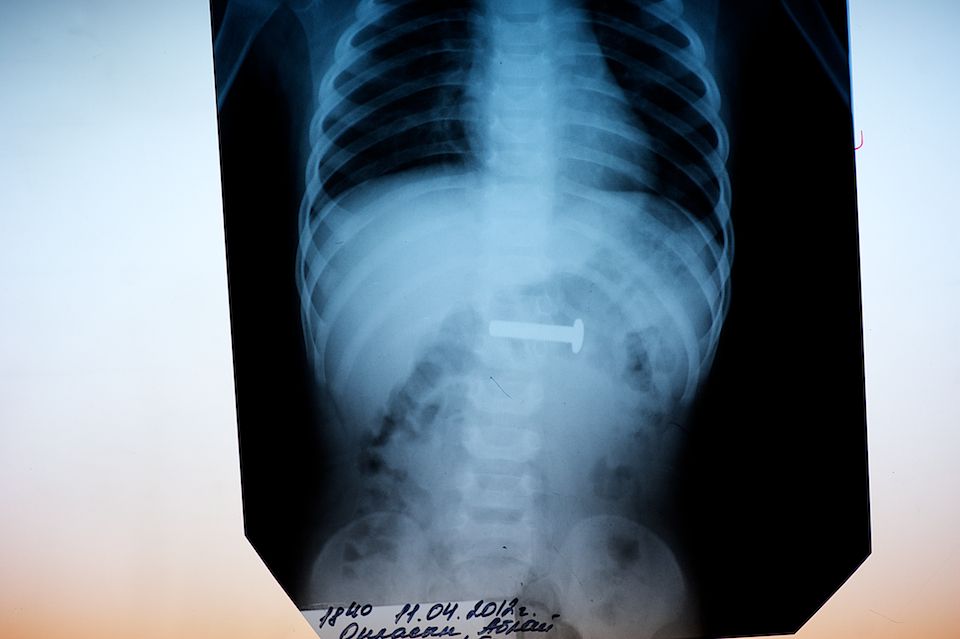

3-сантиметровый болт был благополучно извлечен из желудка ребенка с помощью эндоскопического зонда. Рентген-снимок с обнаруженным инородным телом.